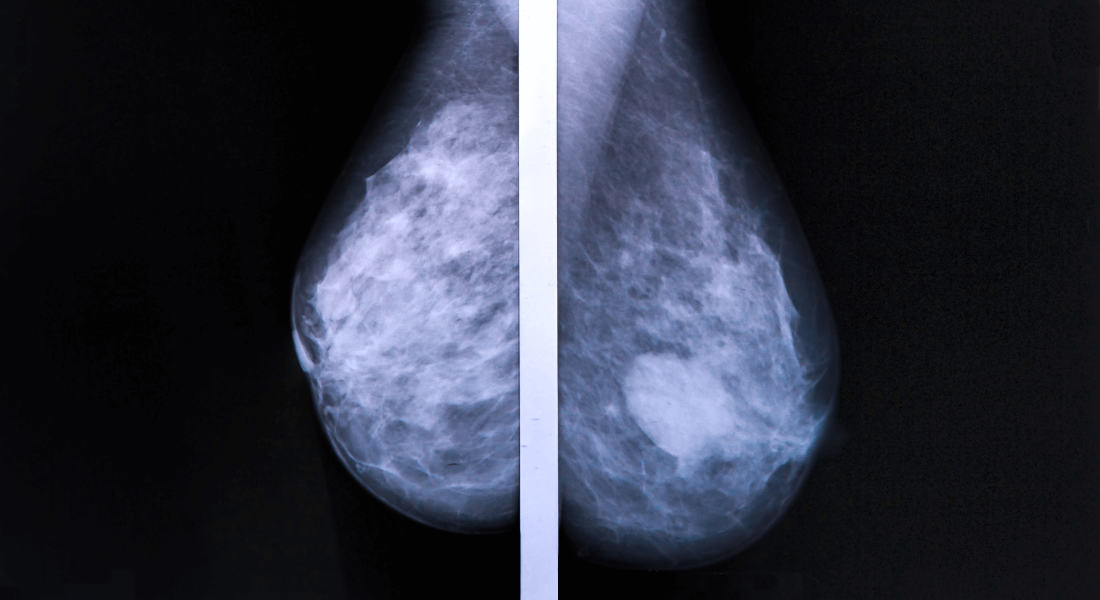

New Discovery May Pave The Way For More Targeted Treatment Of Cancer Patients

CANCER Women with certain mutations in BRCA2 have an increased risk of breast and ovarian cancer. In a new study, researchers from the University of Copenhagen show that BRCA2 requires a specific enzyme in order to repair DNA damage. The result can pave the way for more targeted treatment of a group of cancer patients with mutations in BRCA2.